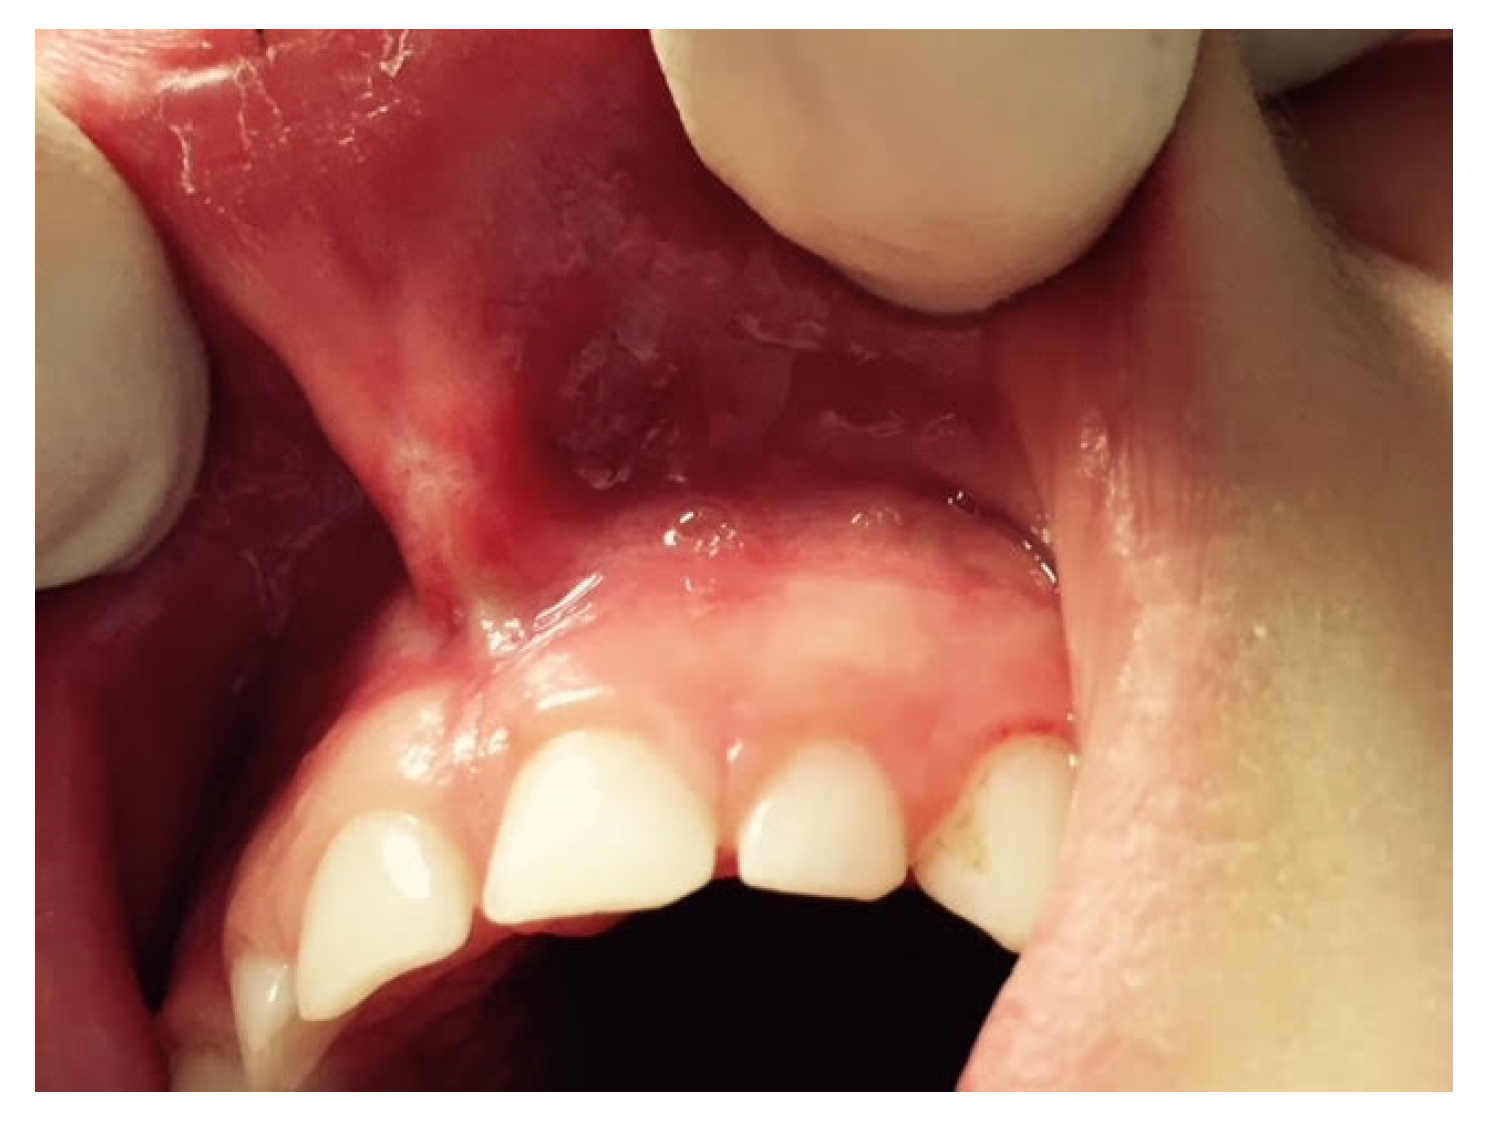

A characteristic of an abnormal frenulum, known as “pull syndrome,” is the ischemization of the palatine papilla and mesial gingival borders of the upper central incisors after traction of the top lip (Figure 1).

Figure 1.

Example of the hypertonic ULF.